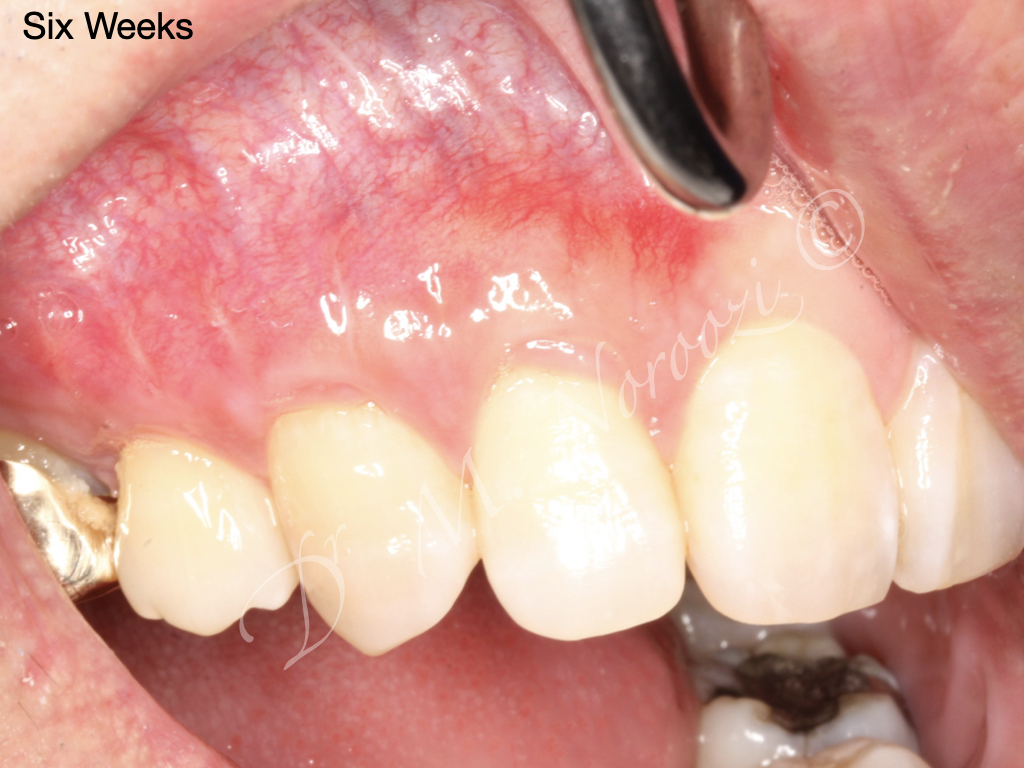

Allograft Dermal with Pinhole Surgery, Alternative to Gum Grafting